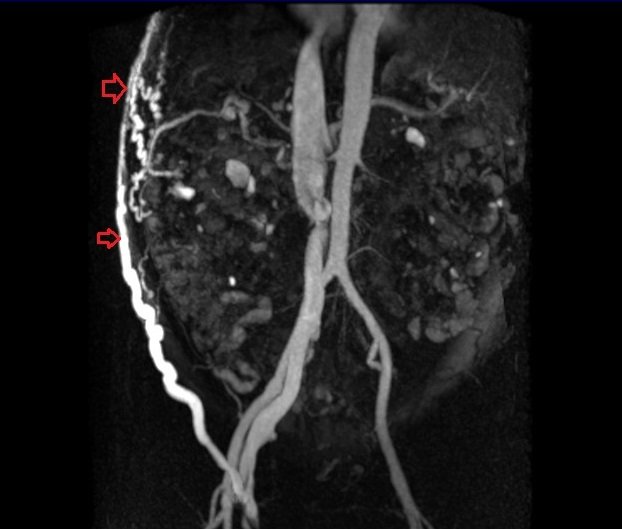

MRI abdominal pathologies FNH LIVER Haemangiomas Liver Choledocholithiasis Renal cell carcinoma Abdominal Wall AVM Gallstones Retroperitoneal desmoid Hepatocellular carcinoma (HCC)